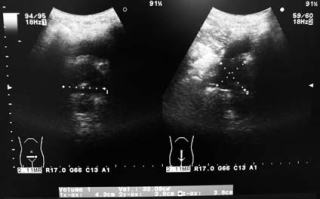

半年前のエコー

前立腺は32mlと測定されています。残尿はなし。

今回の膀胱エコー

膀胱は導尿後ですが、膀胱内に沈殿が描出されています。

今回の前立腺エコー

前立腺は20mlと測定されました。